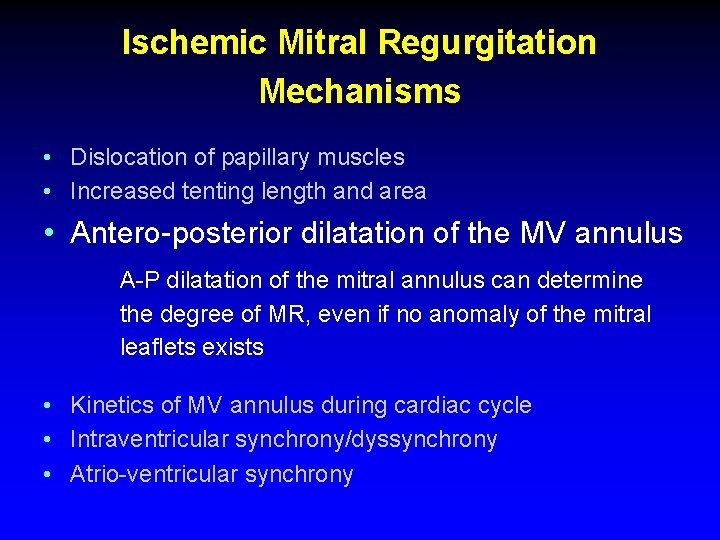

Ischemic Mitral Regurgitation Mechanisms • Dislocation of papillary muscles • Increased tenting length and area • Antero-posterior dilatation of the MV annulus • Kinetics of MV annulus during cardiac cycle • Intraventricular synchrony/dyssynchrony • Atrio-ventricular synchrony

Ischemic Mitral Regurgitation Mechanisms • Dislocation of papillary muscles • Increased tenting length and area • Antero-posterior dilatation of the MV annulus A-P dilatation of the mitral annulus can determine the degree of MR, even if no anomaly of the mitral leaflets exists • Kinetics of MV annulus during cardiac cycle • Intraventricular synchrony/dyssynchrony • Atrio-ventricular synchrony